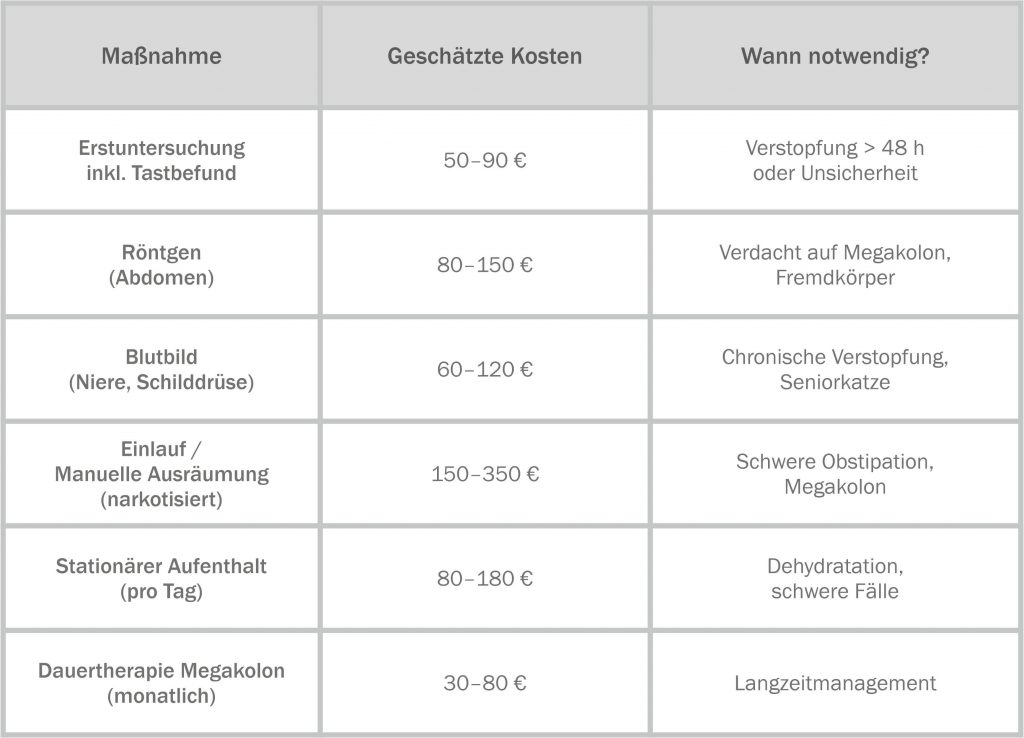

Kosten-Transparenz: Was kommt auf dich zu? (Stand 2026)

Je nach Schweregrad können durch Verstopfung sehr unterschiedliche Kosten entstehen. Die folgende Tabelle dient als Orientierungshilfe. Bitte beachte, dass die tatsächlichen Kosten von der Region, der Praxis und dem individuellen Befund abhängen.

Ein Hinweis zur Planung: Eine Katzenversicherung kann bei chronischen Erkrankungen oder häufiger tierärztlicher Behandlung sinnvoll sein.